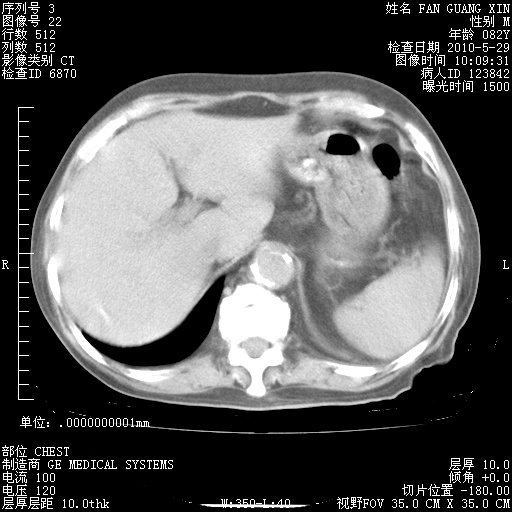

再治疗10天后的肺部CT 纵膈窗